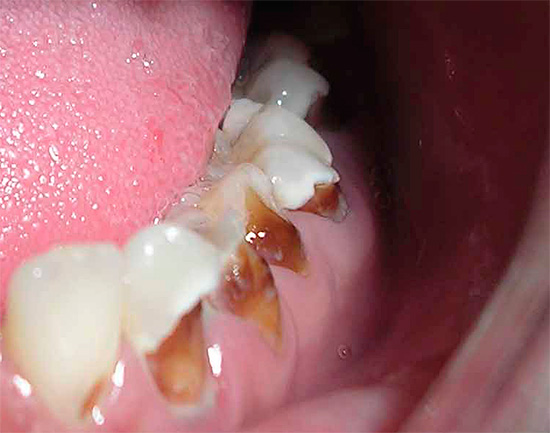

Oggi, a causa della popolarità della cura orale e della disponibilità di servizi dentali, la malattia è diventata meno comune, ma il problema è ancora rilevante nelle aree rurali e nei bambini in età scolare, quando quasi tutti i denti di un bambino sono affetti da carie (vedi l'esempio nella foto), e i genitori non sanno cosa fare in una situazione del genere.

Oltre al fatto che la carie è pericolosa per la salute, provoca dolore e limita la scelta del cibo, è anche un grave problema estetico. La foto sotto mostra un esempio di carie generalizzata:

La foto sotto mostra un altro esempio di corsa carie dei denti decidui in un bambino:

Molto spesso, questa situazione si osserva nei bambini che hanno avuto malattie infettive acute, soffrono di varie malattie croniche e hanno difetti cardiaci congeniti.

Un'alta prevalenza di carie generalizzata si osserva nei bambini con tonsillite, scarlattina, che soffrono di reumatismi cronici, glomerulonefrite, malattia di Little, sindrome di Down e malattia del marmo.